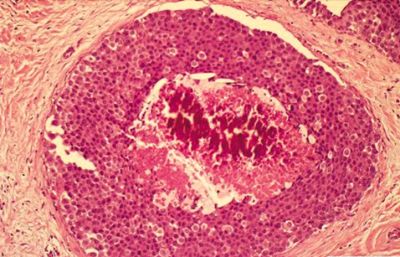

תהליך זה המתקדם וממלא את כל צינורית החלב ובו זמנית מאבד את התאים המיואפיתליאלים שלו, הופך להיות Ductal carcinoma in situ (DCIS) (תמונה 29.12) או בבועית החלב Lobular carcinoma in situ (LCIS)(תמונה 30.12).

ה- DCIS היא השאת הממארת הכי מוקדמת שניתן לגלות כיום. היא מתאפיינת בהיותה מחלה מקומית של השד אשר נדיר כי מערבת בלוטות או שולחת גרורות. לכן הטיפול במחלה זו הוא מקומי. במידה והנגע הזה נשאר, כ-30% יפתחו את הצורה התוקפנית יותר של סרטן השד והיא ה- Invasive carcinoma (IC). בנגעים אלה, מתפתחות קבוצות (קלון) של תאים בעלי יכולת לפרוץ מחוץ לצינורית החלב אל השומן מסביב ולשרוד שם (תמונה 31.12 -33.12).

תאים אלה יכולים לנדוד גם לבלוטות הלימפה או להיהפך לגרורות באיברים אחרים. למעשה, המעבר מ-DCIS ל-IC הוא מעבר ממחלה מקומית למחלה אזורית-מערכתית. ב-70% מהחולות המאובחנות בשלבים מוקדמים (Stage I, II) המחלה היא מקומית-איזורית, ואילו ל-30% יש מחלה מערכתית. החלוקה של סוגי השאתות השונות לפולשנית/ לא פולשנית והדרגה מוצגת בגרף 7.12: